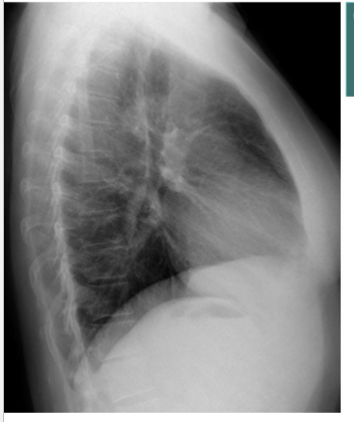

Identify costophrenic angles (post + ant)

yes